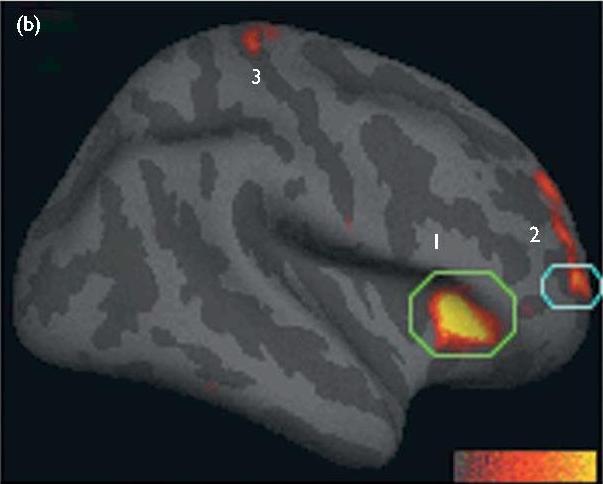

「島皮質」は,ヨガを行いながら体内の変化に意識を向け続けることで肥大化することが科学的にも証明されています↓

(Lazar, 2005) 1: 島皮質 2: 背内側前頭前野

つまり,周りの人たちとポーズの優劣を競い合うのではなく,目を閉じ「今ここ」に意識を向ける必要があります.